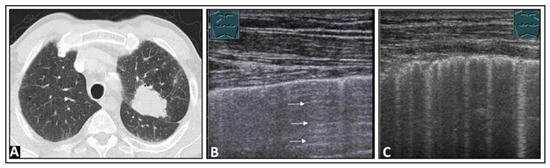

5. Pneumonia

7. Other Pathologic Situations